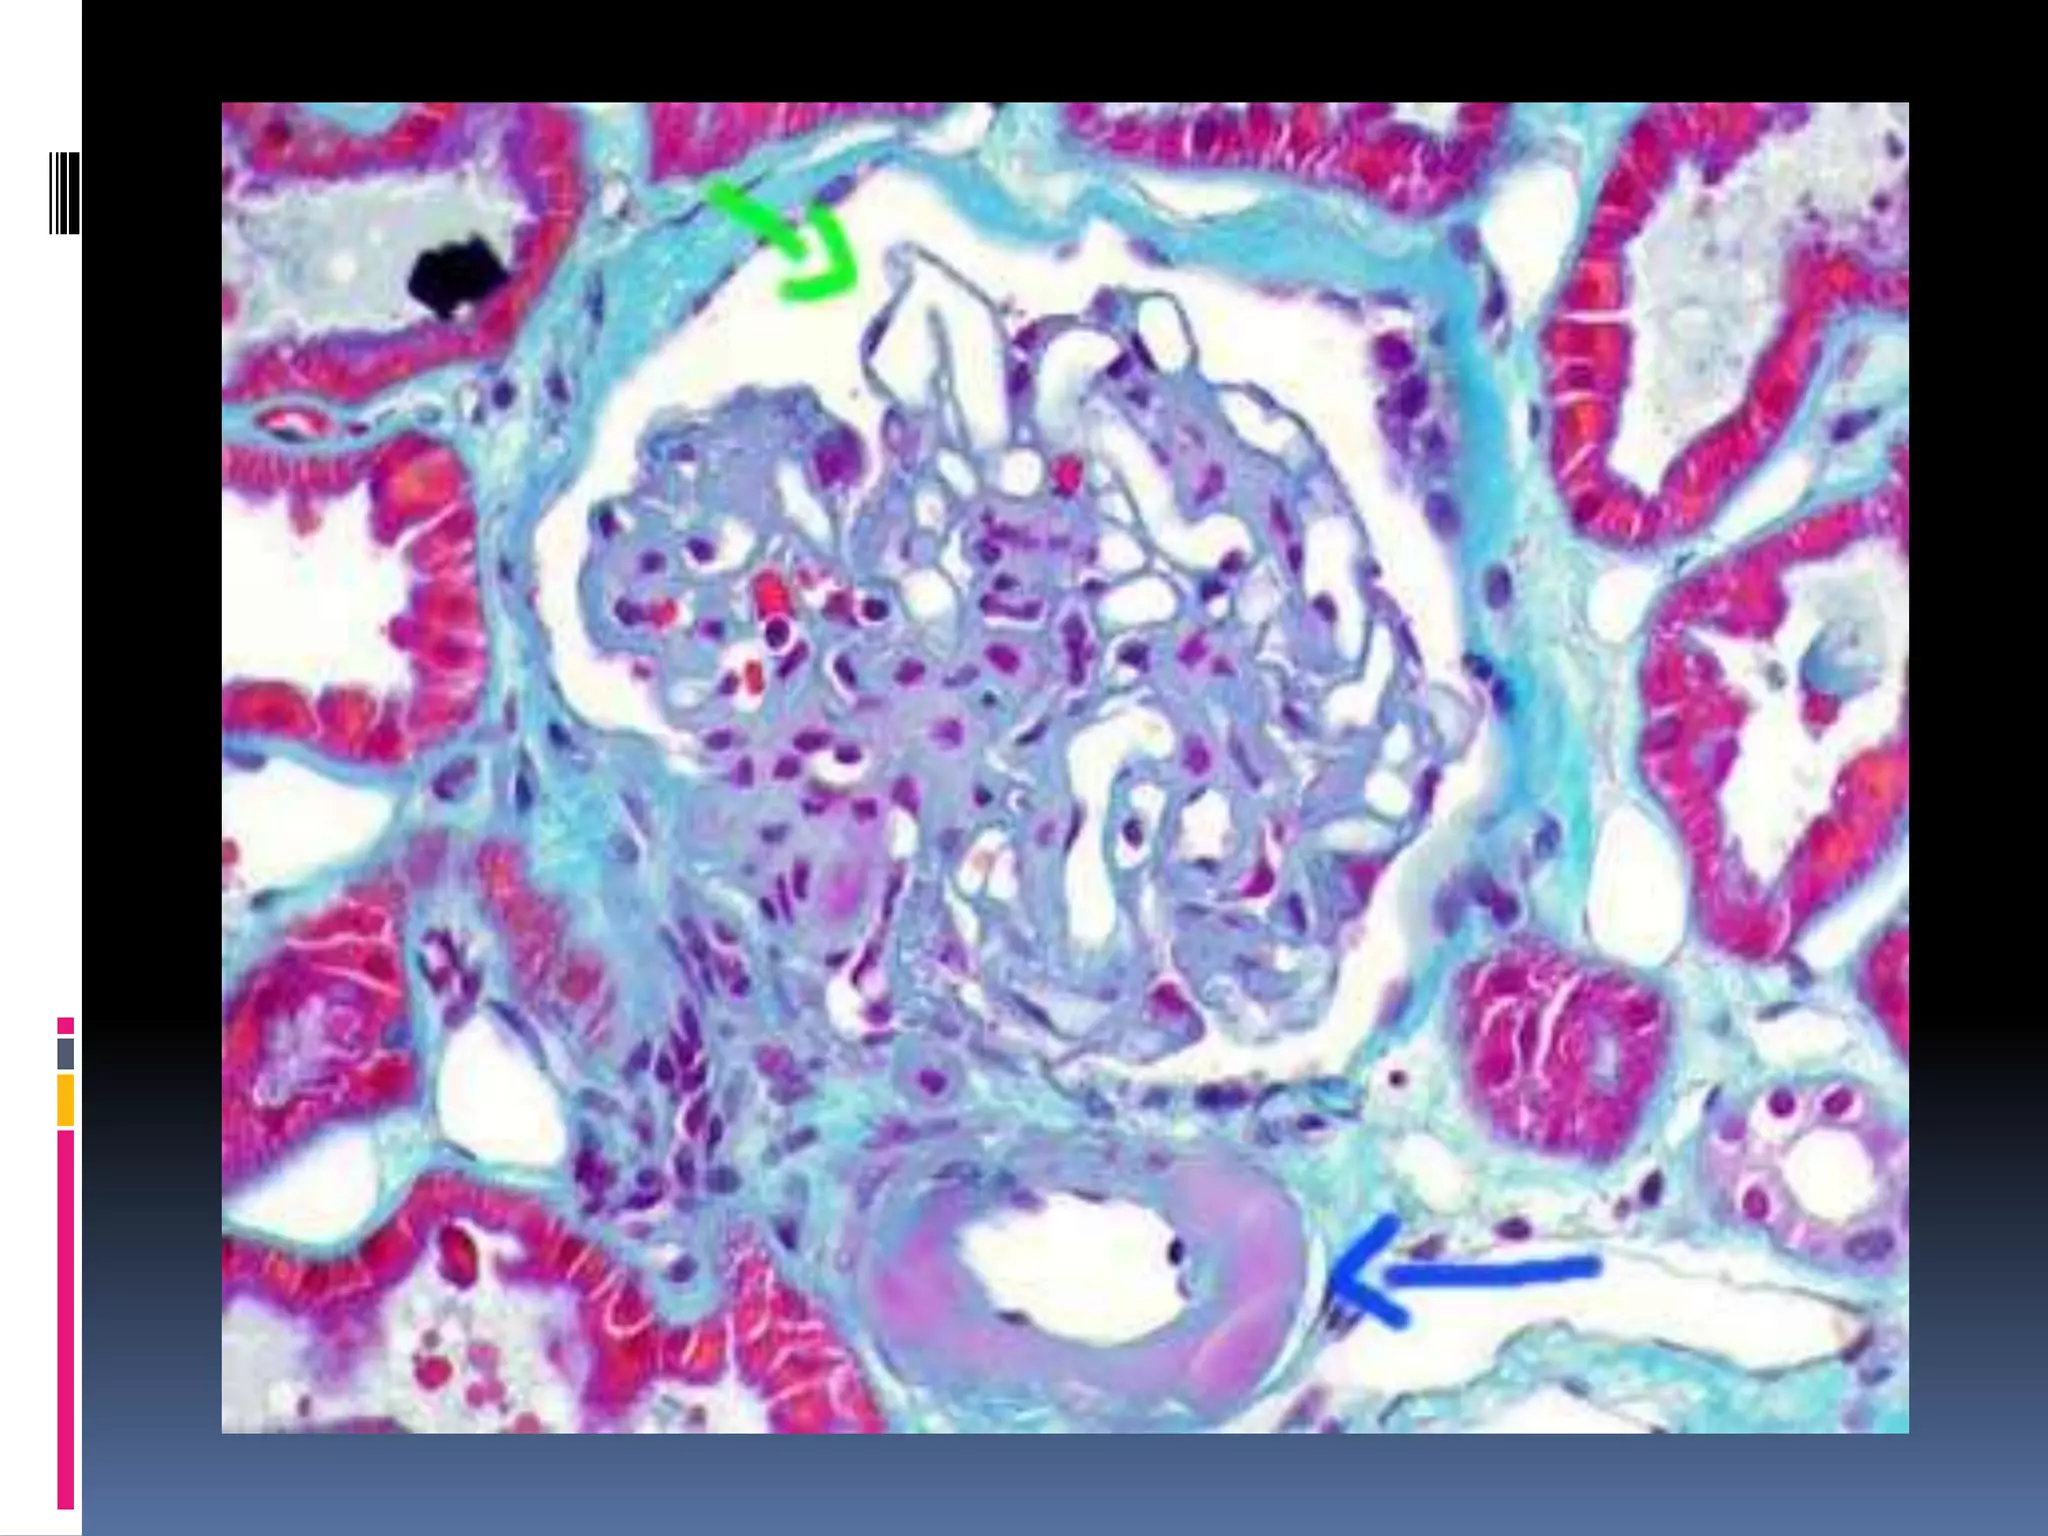

BRAIN STORMING

Arteriolar

Hyalinosis

Capsular

Drops

Micro-

Aneurisms

TRICHROME STAINING IN AYMLOIDOSIS: